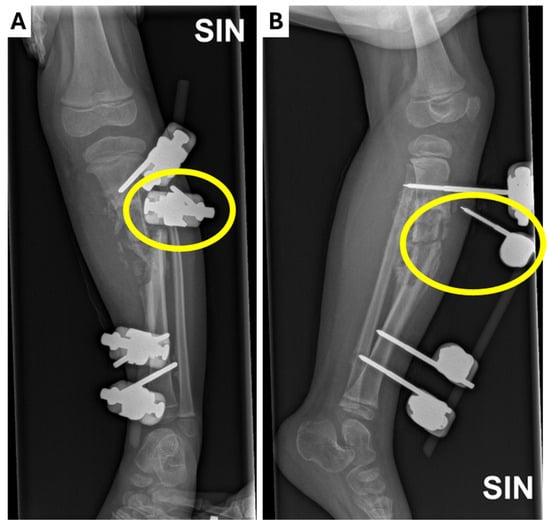

Approximately 3 months after the last hospitalization, the patient presented again as an acute patient with complaints of subfebrile body temperature and discomfort in the left hip joint, refusing to lean on the left leg. Inflammatory markers were elevated (CRP: 106 mg/dl). The localized wound on the lateral surface of the left thigh did not heal and wound and blood samples were taken for culture. Both were negative for microflora. An X-ray examination was conducted on the patient’s left hip joint, femur, and knee joint (Figure 6). Antibacterial therapy with vancomycin at 300 mg i/v three times a day, cefotaxime at 750 mg three times a day, and oxacillin at 550 mg four times a day was initiated. The patient’s condition gradually improved after six days of antibacterial therapy, and no new foci of osteomyelitis were found. The patient resumed leaning on her left leg and was discharged from the hospital with recommendations to continue using a rigid orthosis and to continue regular bandaging of the wound.

Figure 6.

X-ray examination of the (A,B) left hip joint and (C,D) femur and knee joint in anterior–posterior and lateral projections showing a small, heterogeneous lateral condyle of the femur, a lytic zone in the metaphysis, massive calcification in the mid-diaphysis, a normal hip joint gap, smooth surfaces, and no pathologies in the hip joint bones.